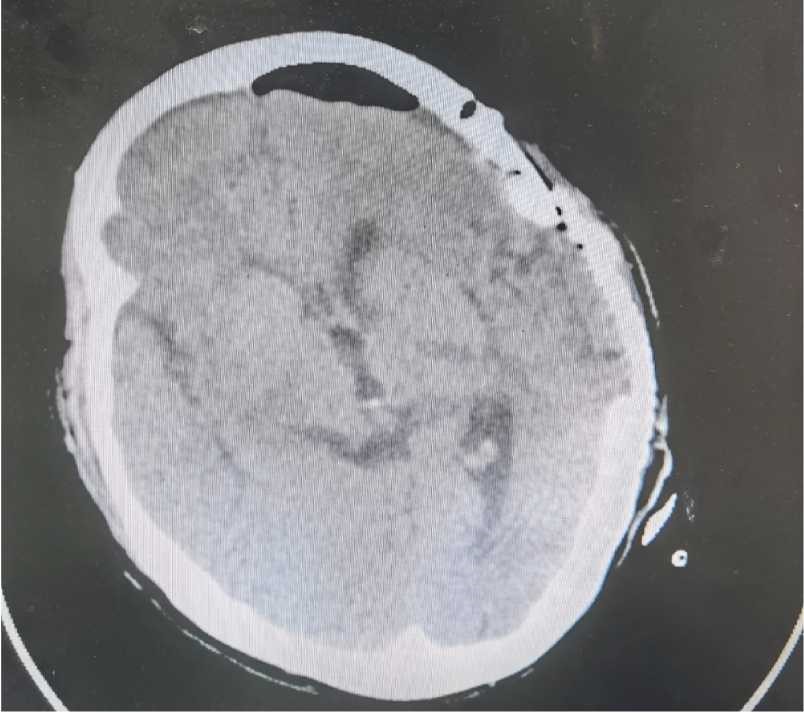

查患者浅昏迷,GCS12分,四肢肌力正常。急查头CT:显示颅内出血破入脑室。给患者行侧脑室引流术。待血肿吸收后行DSA 检查。

CT显示左侧颞叶出血破入脑室